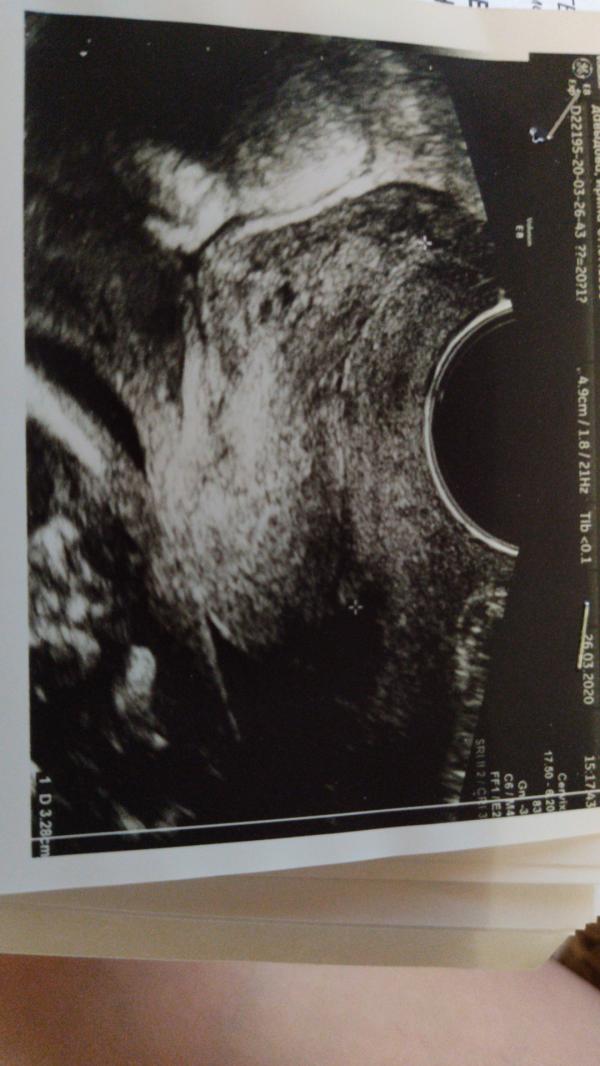

Привет всем))) помогите, просто я вообще не понимаю что тут изображено, сколько не смотрела не понимаю)))

Сильно размытая моська:) сорян) личико:) ну по крайней мере моя фантазия так показывает)

@zlovredina вроде как вообще на УЗИ сказали что тут пол видно, но на пол ребенка точно не похоже😅

Не чего не вижу,ой мне завтра идти, боюсь что по такой фото я точно не чего не пойму